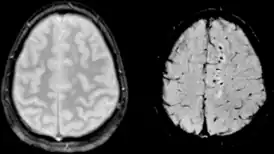

Диффузное аксональное повреждение на МРТ в режиме GRE (слева) и SWI (справа)

При диффузном аксональном повреждении головного мозга микроскопические мелкоочаговые кровоизлияния выявляются в мозолистом теле, полуовальном центре, верхних отделах ствола мозга. Клинически оно проявляется длительной комой, которая в большинстве случаев переходит в вегетативное состояние. Последнее характеризуется отсутствием корковой деятельности и длится месяцы и годы.